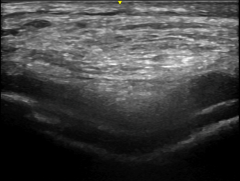

Musculoskeletal ultrasonography is a safe and painless imaging technique that uses soundwaves to evaluate bones, tendons, ligaments, nerves, and the joint as a whole. It does not use radiation and can be done even in pregnant women. This is a specialized exam performed in “real time” by a physician trained in MSK ultrasound.

An ultrasound gel is applied on the skin and the joint is scanned by moving the ultrasound probe to look for evidence of disease or inflammation. During the exam, you may be asked to move the joint so we can better evaluate the muscle, tendon, or ligament involved. Your doctor will be able to see the images of your joint through the screen and can discuss the findings with you as they see them.

Using MSK ultrasound, we can diagnose a range of musculoskeletal conditions including tendonitis, bursitis, carpal tunnel syndrome, gout, pseudogout, and inflammatory changes seen in rheumatoid arthritis or psoriatic arthritis.